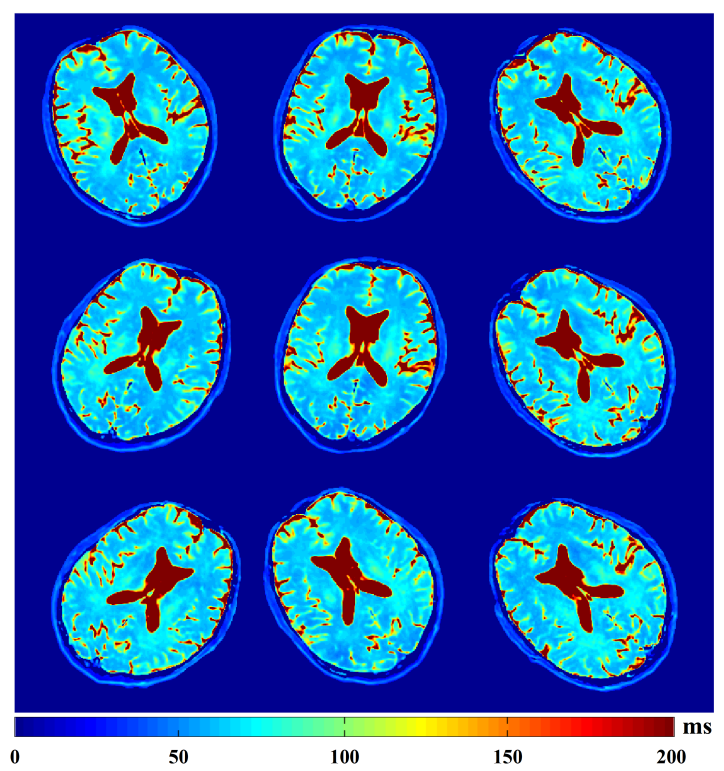

图2. 随机运动下的人脑定量T2成像结果

多个健康志愿者数据表明,基于模型的合成数据驱动学习策略可以有效减轻OLED-T2定量图像中由头部运动产生的奈奎斯特伪影和条状伪影,并保持定量精度。该框架还被应用于临床儿童癫痫患者,结果表明其对运动的抵抗能力显著优于现有的常规MRI方法。